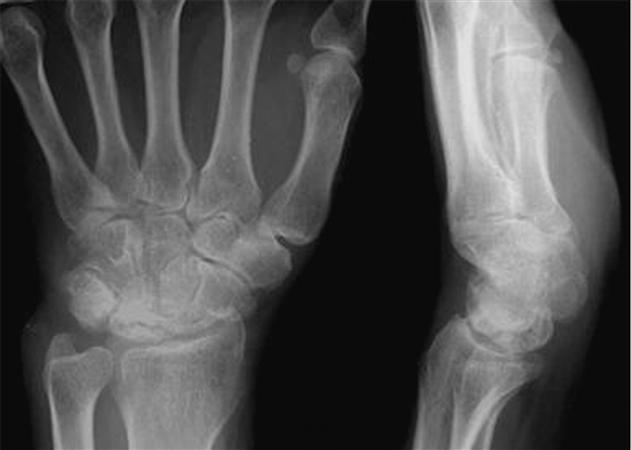

Stage III 부터는 주상골도 영향을 받기 시작하며 회전을 하거나(IIIA, cortical ring 관찰가능), carpal height 가 줄어드는 것을 확인할 수 있습니다. (IIIB), IIIA 까지는 II와 치료를 거의 동일하게 하지만, IIIB 부터는 Proximal row carpectomy 나 STT, SC fusion 등을 시행해 볼 수 있습니다.

치료 중에 IIIB 부터 시행하는 치료는 아래와 같습니다.